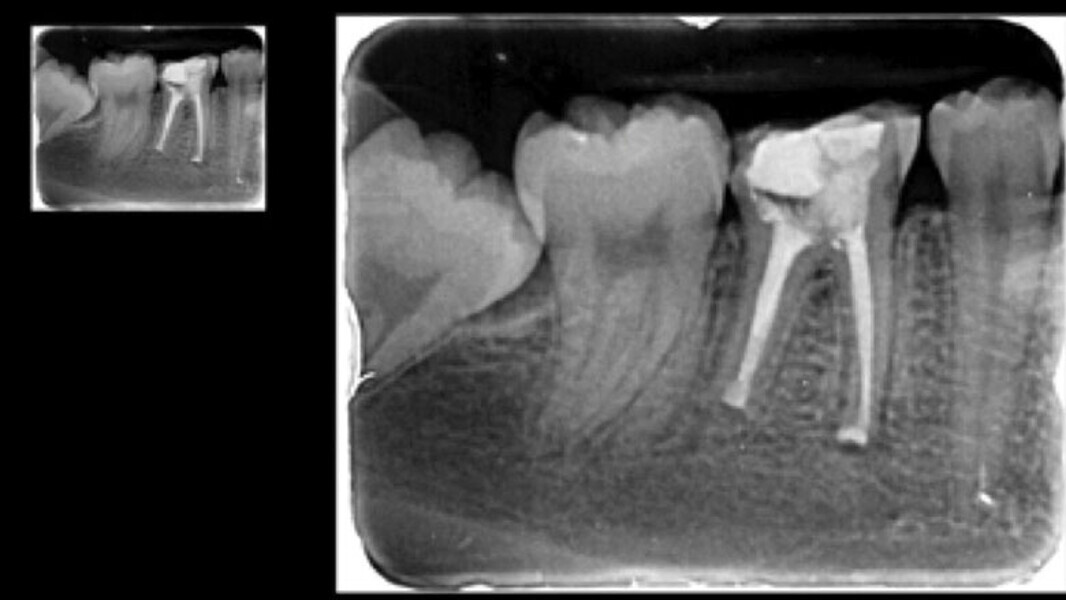

Fig. 2. Estado tras la revisión, la colocación de la espiga y la reconstrucción.

Fig. 3. Durante la preparación se procuró no dejar ningún borde afilado en la cavidad.